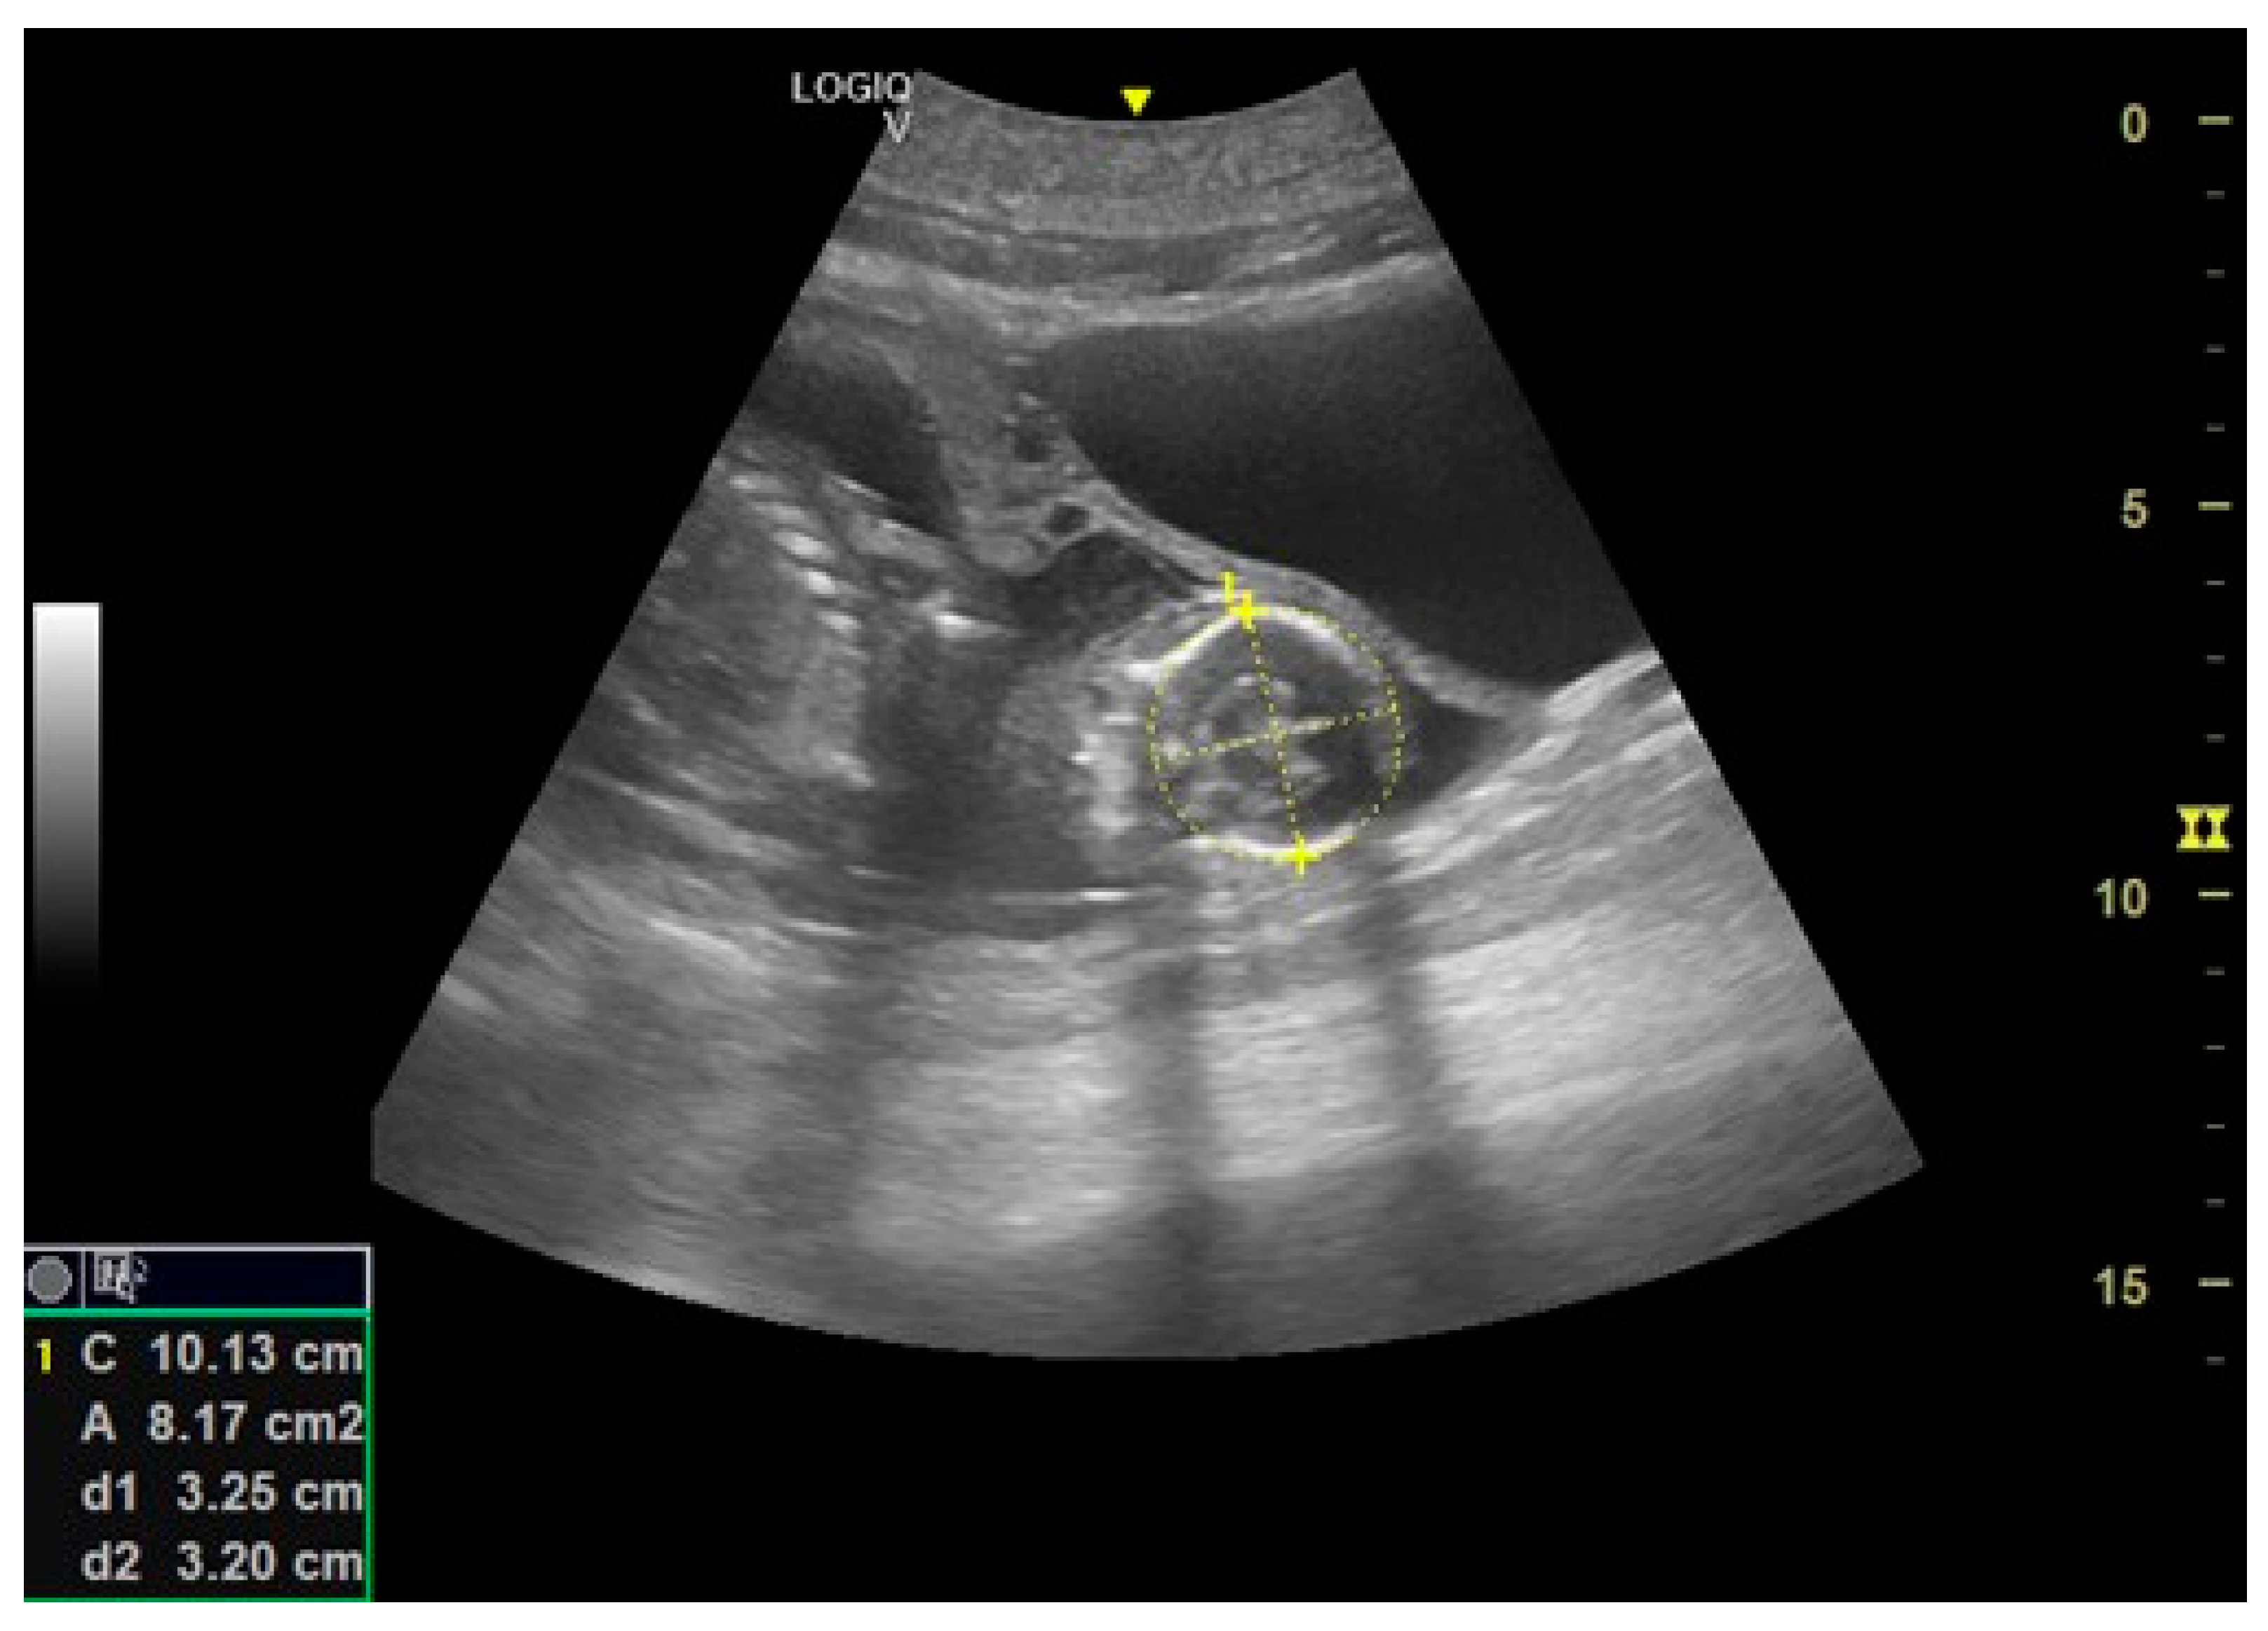

- Day 197: The umbilical cord is already seen like a hyperechoic cord form structure; it is important to identify the course, and to evaluate the internal vascular components and the absence of knots or torsions until the birth (Figure 5).